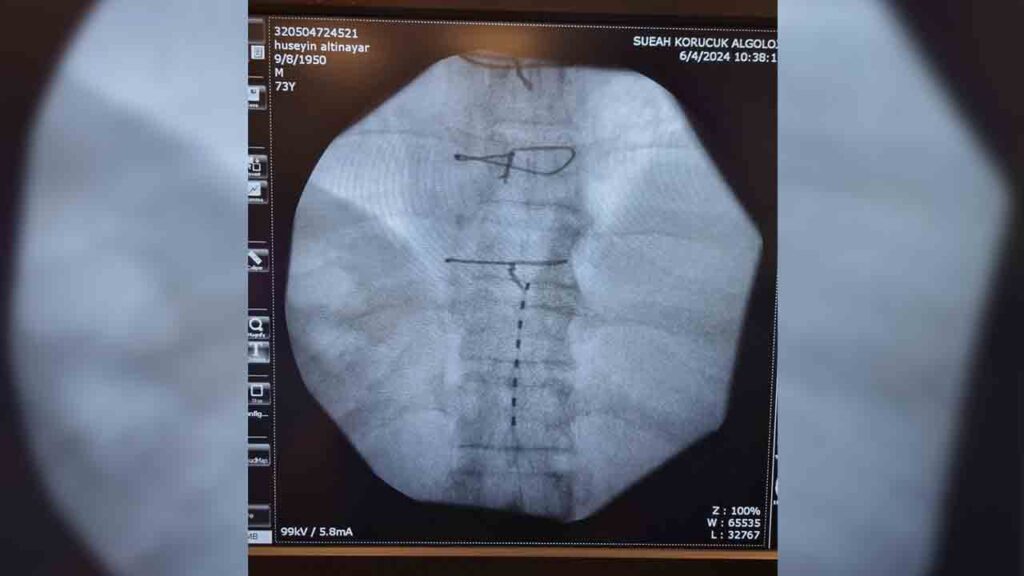

Yıllardır ayağındaki ağrıya çare bulamayan hasta Sakarya Eğitim ve Araştırma Hastanesi (SEAH) Algoloji Kliniğine başvurdu. 7 yıldır ayağında yanma ve ağrı şikayeti (Kronik nöropatik hastalığı) olduğunu belirten hastanın şikayetlerinin son bulması için klinik hekimleri tarafından özellikli bir işlem olan Ağrı Pili (Spinal Kord Stimülatörü) uygulanmasına karar verildi.

Algoloji Kliniğinde Prof. Dr. Kemal Nas, Doç. Dr. Savaş Şencan, Uzm. Dr. Rıdvan Işık ve Asistan Dr. Sena Ünver tarafından işleme alınan hastanın operasyonu başarıyla tamamlandı. İşlem sonrası servise alınan hastanın uzun yıllardır hayatını olumsuz etkileyen müzmin ayak ağrısın geçtiği belirtilirken, ağrı uzmanı hekimler tarafından uygulanan yöntemin son derece etkili bir tedavi olduğu kaydedildi. Şifayı SEAH’ta bulan hastada hayat konforunu etkileyen ağrıdan kurtulduğu için çok mutlu olduğunu dile getirdi.